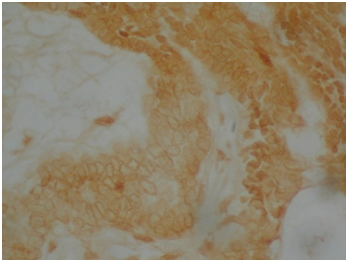

Craniopharyngioma are histologically a benign neoplasm that occurs in the sellar and suprasellar region, with an infiltrative growth pattern, accounts for 1.2-4.6% of all intracranial tumors.1 They are the most common non-neuroepithelial intracerebral neoplasm in children accounting for 5-10% of intracranial tumors in this age group. A bimodal age distribution of ACP is observed, with peaks in children aged 5-15years and adults 45-60years.1 They are often difficult to excise surgically, and they have a 10% to 40% recurrence rate.2 There are at two types of craniopharyngioma: Adamantinomatous craniopharyngioma (ACP) and papillary craniopharyngioma (PCP). Both have distinct morphology and different clinical behavior. ACP has at least four different squamous histological areas: superficial mature squamous (SMS), loosely cohesive aggregates of squamous cells known as “stellate reticulum” (SR), palisaded basal columnar (PBC) cells and nodules of wet keratin (WK) (Figure 1, Figure 2 & Figure 3). Cystic cavities containing squamous debris are lined by flattened epithelium. PCP occurs virtually exclusively in adults with mean age of 40-50years.3,4 Histologically, it is different from ACP by lacking nuclear palisading, wet keratin, and dystrophic calcification.5

Figure 2 Wet keratin.